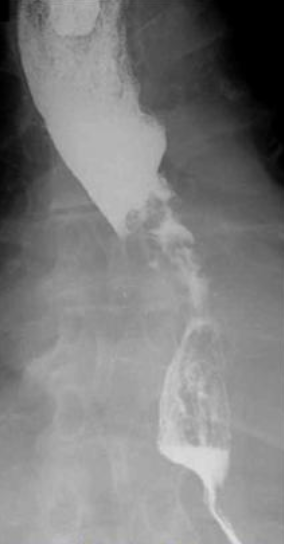

<p>What esophageal disorder is this?</p>

What esophageal disorder is this?

Benign Stricture